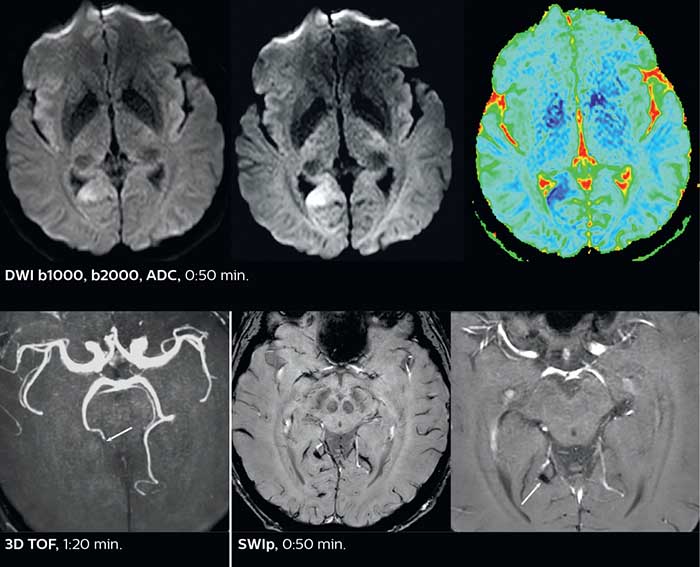

Fast acute stroke protocol

This is an example of acute ischemic stroke with distal occlusion of the right posterior cerebral artery. Note the improved visibility of the ischemic territory on the diffusion weighted image with high b-value. The 3D FLAIR shows a distal PCA occlusion. The fast SWIp depicts the thrombus on the isolated second echo image. The total scan time (including SmartBrain, preparations and a fast 3D T1w TSE Gd) is 8:00 minutes.

The ability to perform more sequences can help in making a swift and confident diagnosis. “For example, our stroke cases usually include the regular sequences that every center does (b1000 diffusion, FLAIR, time-of-flight angiography), but we also image supra aortic vessels, and we can replace a gradient echo sequence with a fast 50-second susceptibility-weighted sequence, and all of this doesn’t add much time. because all the regular sequences are accelerated on Elition.”

Using MultiBand SENSE allowed the staff to improve their diffusion quality. “Our diffusion sequence was already fast before, about 40 seconds. Now with Elition, it still lasts 40 seconds, but we improved the spatial resolution by 0.2 mm and use high b-values to be more sensitive to visualize changes related to acute stroke,” says Dr. Savatovsky.